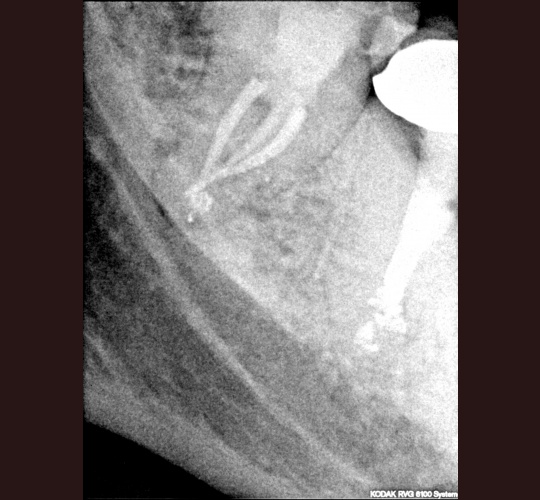

Read MoreEndodontic Treatment: Case #4 – Patient presented for root canal therapy referred to our office due to complex root anatomy.

Most notable about this case was that the canals were severely curved and almost a 90 degree on the back (distal canal) with lots of sealer puffs on all the roots.